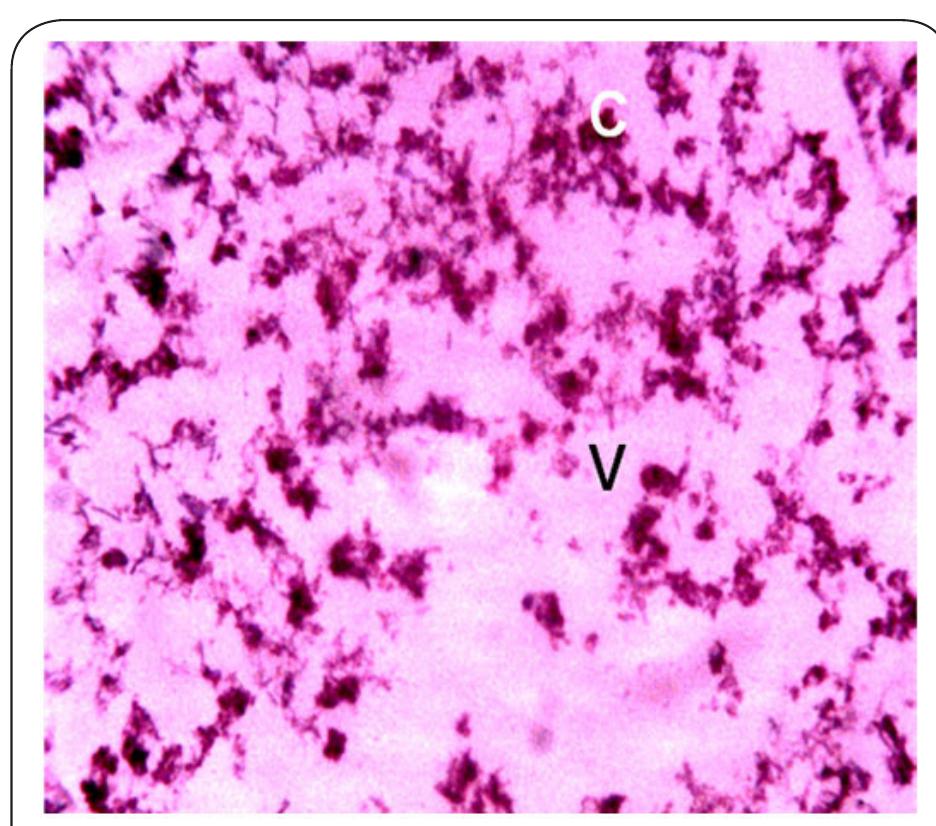

Dr. Ozovehe Patrick Samuel - FEDERAL UNIVERSITY OF TECHNOLOGY, MINNA-NIGERIA